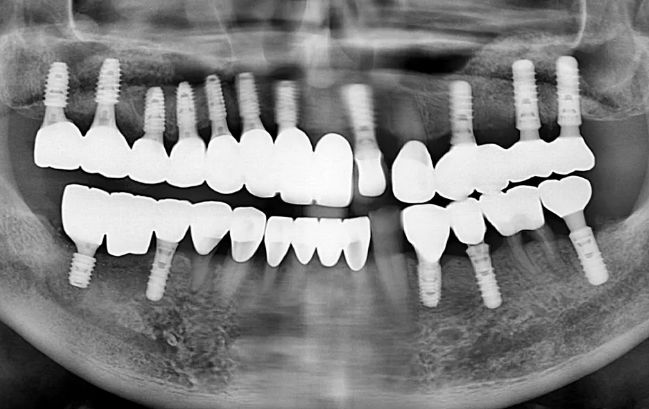

50대 남성, 원데이 전체 임플란트 18개 식립